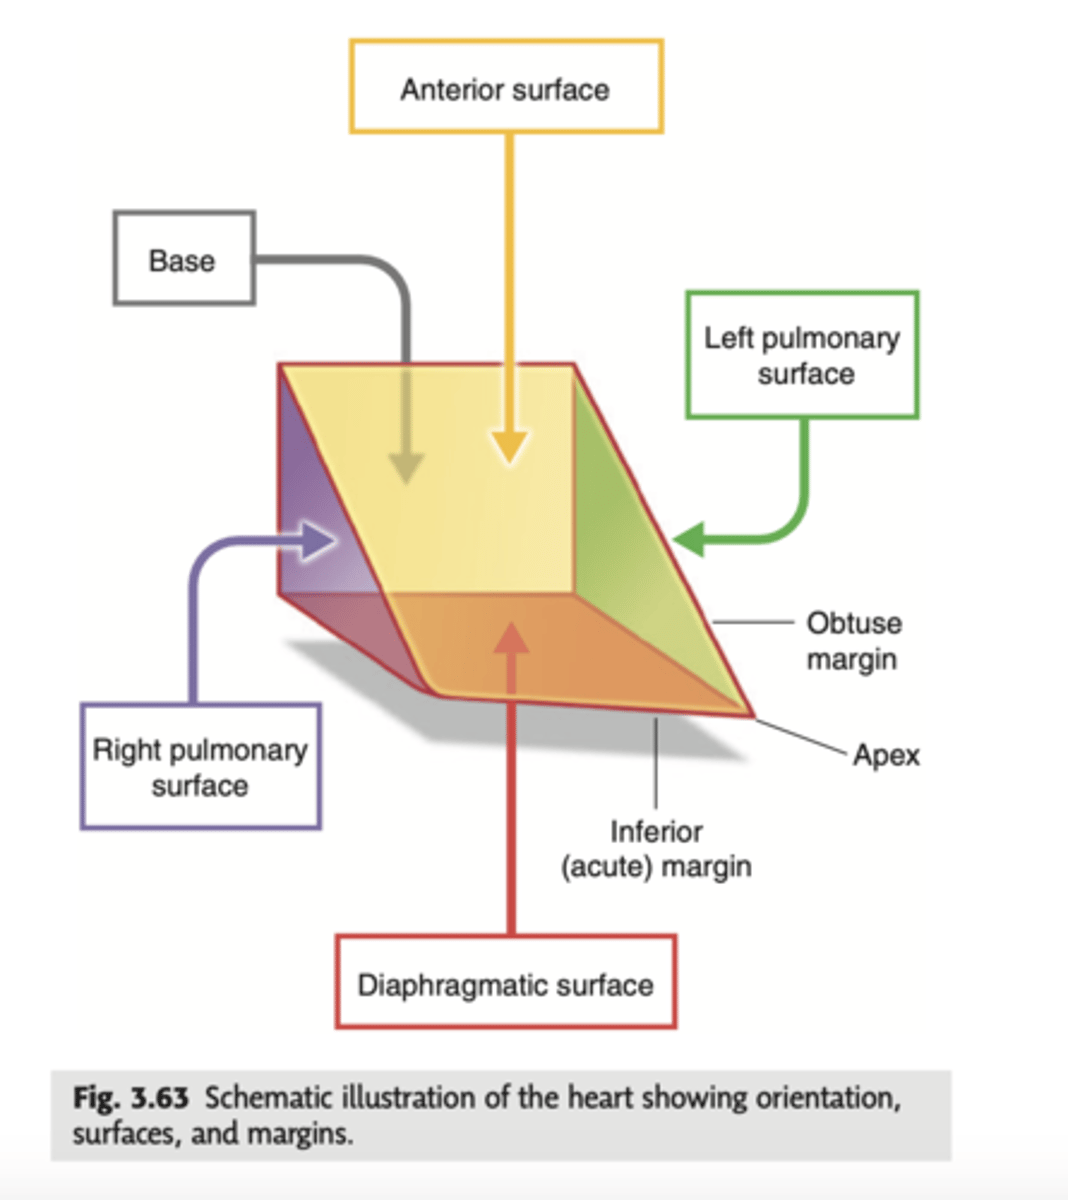

How is the heart's shape described and what are its surfaces?

The heart has an inverted pyramidal shape lying in one side.

Surfaces:

. Inferior diaphragmatic surface

. Sternocostal surface or anterior surface (corresponds mainly to the right ventricle)

. Posterior surface (corresponds to the ventricles, mainly to the left one)

. Right pulmonary surface

. Left pulmonary surface

Describe the apex in the heart's anterior view

. Point to left side, downwards.

. At the level of the 5th intercostal space (we will auscultate the apex of the left ventricle)

APEX: HIGHEST POINT, VERTEX.